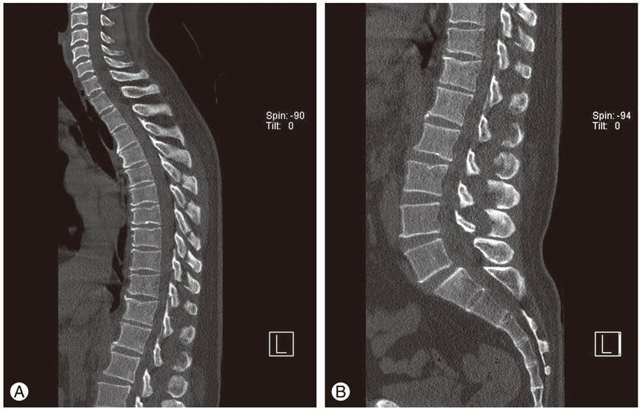

- рентген, КТ и МРТ для поиска изменений в костях, межпозвоночном пространстве, мягких тканях.

В большинстве случаев первое диагностическое мероприятие, которое назначают при обращении с болью в спине, – рентген. Исследование позволяет выявить патологические процессы, протекающие в позвоночнике на ранней или поздней стадии. Помимо обычного рентгена назначают диагностику с использованием контрастного вещества:

Для подтверждения диагноза может понадобиться проведение компьютерной или магнитно-резонансной томографии. Для выявления признаков воспалительного процесса в организме назначают лабораторные исследования: анализы крови, мочи.